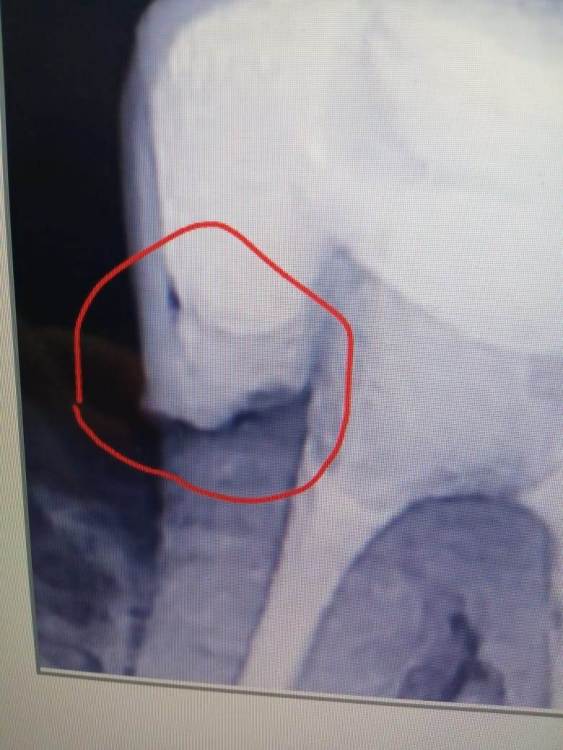

Aleksandr21321 Опубликовано 1 февраля, 2024 Поделиться Опубликовано 1 февраля, 2024 (изменено) Посмотрев на данные снимки, пользователи данного форума посоветовали сходить к стоматологу, ведь возможно тут вторичный кариес. (Снимки ниже) Я сходил к доку и вот диалог с ним: - Здравствуйте, стоматолог! Это вторичный кариес на снимках? - Сначла дам комментарий по поводу синего снимка. Пломба была поставлена в другом месте, не у нас. У вас зуб разболелся и я просто открыл каналы и удалил нерв и закрыл шахту обратно. Там я не высверливал потому что визуально смысла не было. Там все герметично переживать не о чем - А что по поводу серого снимка, доктор? - Я зачистил до плотных тканей и поставил пломбу. Ничего страшного Скажу честно, я мало что понял из диалога со стоматологом. Кариес это или нет - это вопрос, который все еще меня тревожит. Как думаете, надо искать нового дока или нынешний прав и беспокоиться не стоит? Изменено 1 февраля, 2024 пользователем Aleksandr21321 Ссылка на комментарий